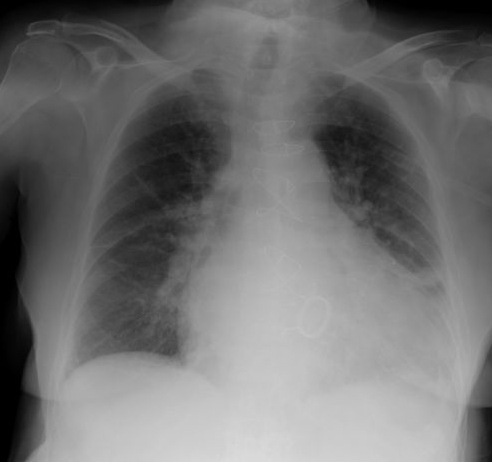

Fibrosis pulmonar. ICC.